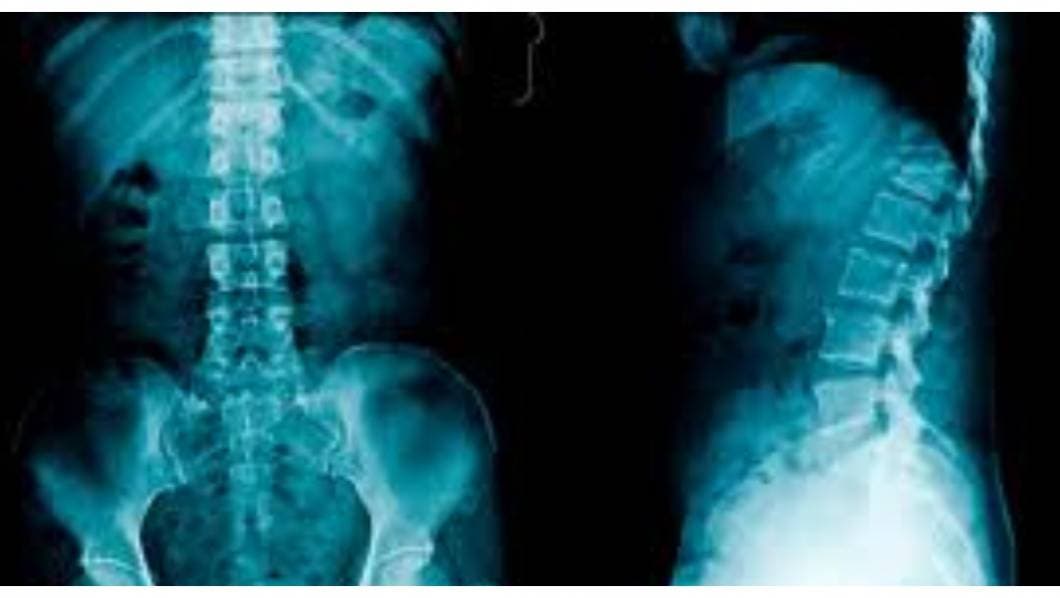

Las radiografías de la columna vertebral son imágenes de la columna vertebral. Pueden tomarse para detectar lesiones o enfermedades que afectan los discos o las articulaciones de la misma. Estos problemas pueden incluir fracturas, infecciones, dislocaciones, tumores, espolones óseos o enfermedad de disco en la columna vertebral.

También se realizan para revisar la curva de la columna vertebral (escoliosis) o para detectar defectos.

La columna vertebral está dividida en cuatro partes, de modo que hay cuatro tipos comunes de radiografías de la columna:

- Radiografía de la columna cervical. Esta prueba de radiografía toma imágenes de los 7 huesos del cuello (cervicales).

- Radiografía de la columna torácica. Toma imágenes de los 12 huesos del pecho (torácicos).

- Radiografía de la columna lumbosacra. Toma imágenes de los 5 huesos de la parte baja de la espalda (vértebras lumbares) y muestra los 5 huesos fusionados en la parte inferior de la columna vertebral (sacro).

- Radiografía del sacro/cóccix. Permite una visión detallada de los 5 huesos fusionados en la parte inferior de la columna vertebral (sacro) y los 4 pequeños huesos del cóccix.

Las radiografías de columna más comunes son de las vértebras cervicales (imágenes de la columna cervical [C]) y de las vértebras lumbosacras (imágenes de la columna lumbosacra [LS]).